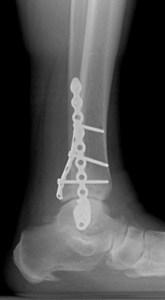

Nonunion and malunion repair related to post-traumatic conditions and/or prior surgery

Acute fracture care of the pelvis and the extremities